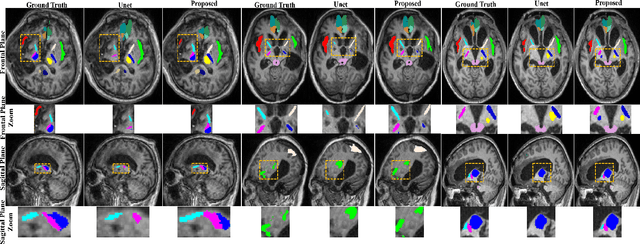

Abstract:Brain magnetic resonance (MR) segmentation for hydrocephalus patients is considered as a challenging work. Encoding the variation of the brain anatomical structures from different individuals cannot be easily achieved. The task becomes even more difficult especially when the image data from hydrocephalus patients are considered, which often have large deformations and differ significantly from the normal subjects. Here, we propose a novel strategy with hard and soft attention modules to solve the segmentation problems for hydrocephalus MR images. Our main contributions are three-fold: 1) the hard-attention module generates coarse segmentation map using multi-atlas-based method and the VoxelMorph tool, which guides subsequent segmentation process and improves its robustness; 2) the soft-attention module incorporates position attention to capture precise context information, which further improves the segmentation accuracy; 3) we validate our method by segmenting insula, thalamus and many other regions-of-interests (ROIs) that are critical to quantify brain MR images of hydrocephalus patients in real clinical scenario. The proposed method achieves much improved robustness and accuracy when segmenting all 17 consciousness-related ROIs with high variations for different subjects. To the best of our knowledge, this is the first work to employ deep learning for solving the brain segmentation problems of hydrocephalus patients.

Abstract:Medical image segmentation is challenging especially in dealing with small dataset of 3D MR images. Encoding the variation of brain anatomical struc-tures from individual subjects cannot be easily achieved, which is further chal-lenged by only a limited number of well labeled subjects for training. In this study, we aim to address the issue of brain MR image segmentation in small da-taset. First, concerning the limited number of training images, we adopt adver-sarial defense to augment the training data and therefore increase the robustness of the network. Second, inspired by the prior knowledge of neural anatomies, we reorganize the segmentation tasks of different regions into several groups in a hierarchical way. Third, the task reorganization extends to the semantic level, as we incorporate an additional object-level classification task to contribute high-order visual features toward the pixel-level segmentation task. In experiments we validate our method by segmenting gray matter, white matter, and several major regions on a challenge dataset. The proposed method with only seven subjects for training can achieve 84.46% of Dice score in the onsite test set.